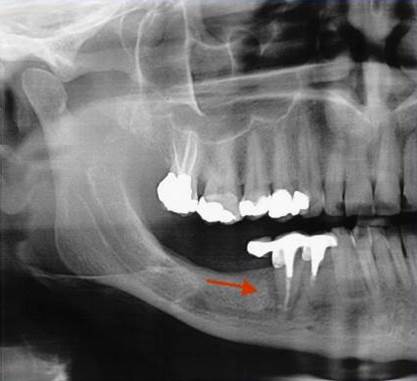

Používá se i v implantologii, při stanovení diagnózy a léčby periimplantitidy (zánětu měkkých tkání a kosti v okolí implantátu).